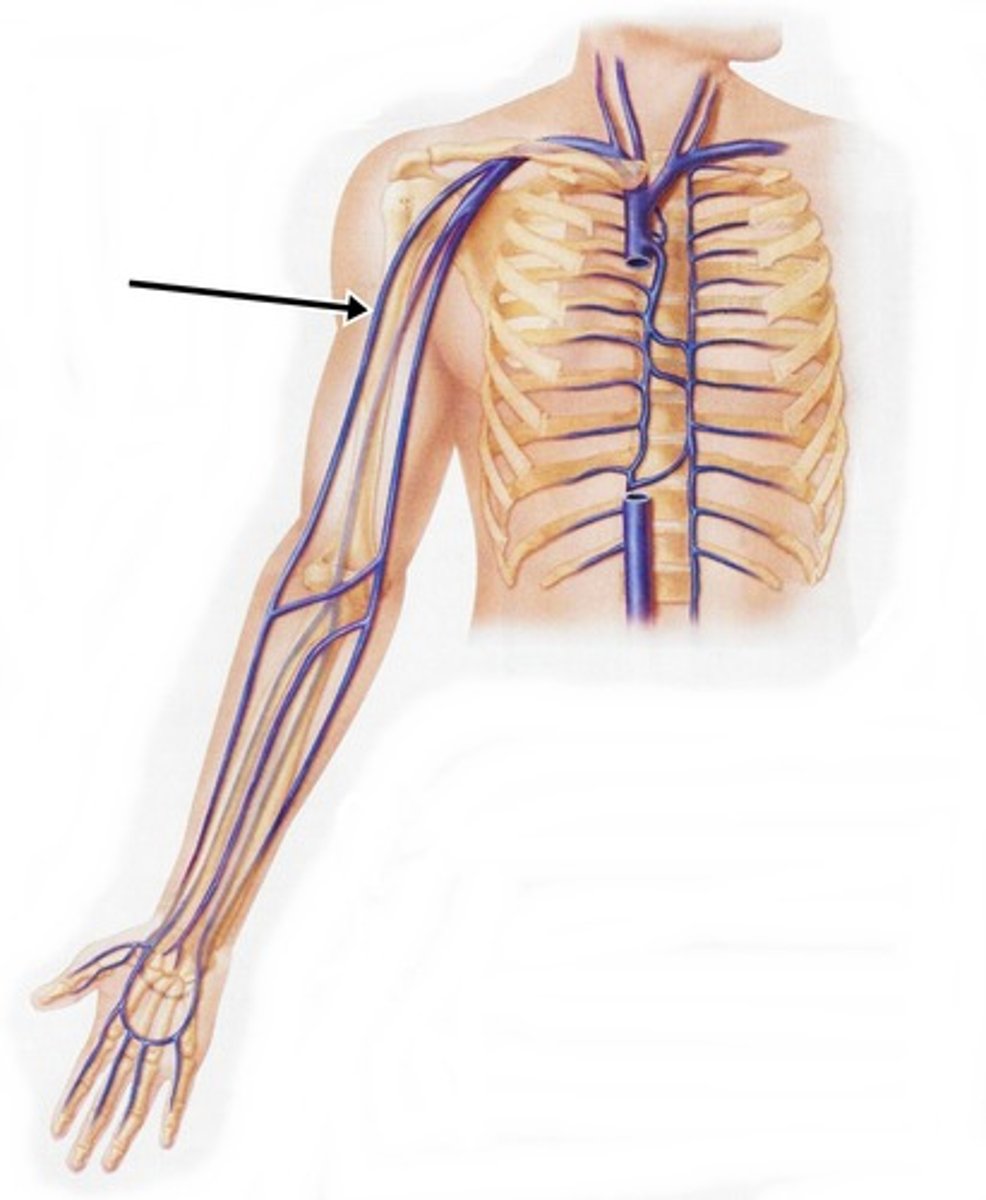

cephalic vein

What is this blood vessel?